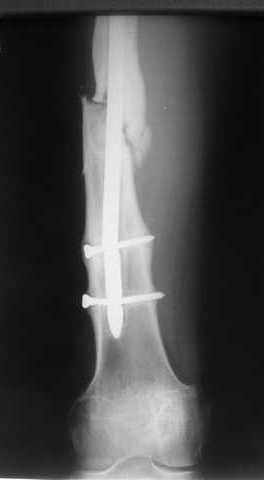

Пациенту М., 30-ти лет, 1,5 года назад в одной из московских больниц был выполнен остеосинтез бедренной кости штифтом UFN (диаметр штифта 9 мм).

К нам больной поступил с признаками ложного сустава бедренной кости, перелома

штифта и дистального блокирующего винта (images 1,2,3).